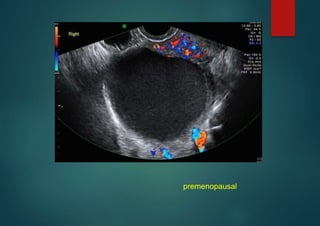

• examples–

premenopausal

Endometrioma

unilocular, ground glass echogenicity,

Simple Descriptors Pattern recognition